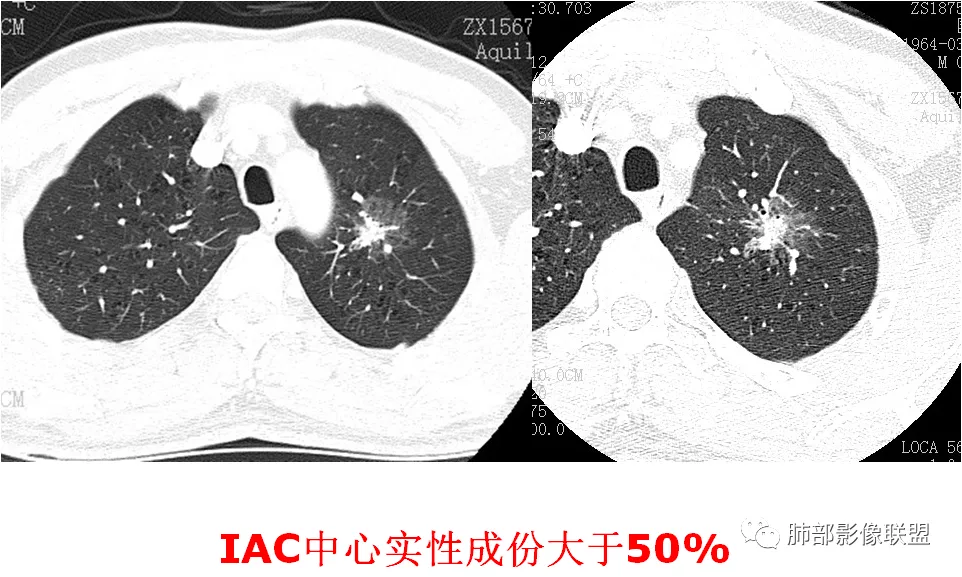

病例(14例)阐述肺部结节的ct诊断策略

肺部实性结节